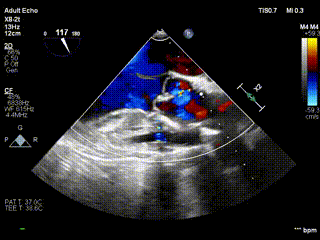

手术全程在全麻下进行,通过右侧股动静脉插管建立体外循环,保障术中血流动力学稳定;心肌保护采用 del-Nido 停跳液,经左右冠状动脉开口顺行灌注,并配合心脏表面冰屑降温,为精细操作创造条件。术中经食道超声实时监测显示:瓣膜修复后闭合良好,无反流信号;术后即刻评估提示,主动脉瓣跨瓣压差正常,左心室流出道通畅,手术达到 “解剖纠正 + 功能恢复” 的双重理想效果。

视频2:病例1术后心超示主动脉瓣无反流,eH 9.8mm,VBR 23.1mm,窦直径29.6mm,窦管交界 25.4mm。

在完成直播手术的基础上,王春生教授团队当日连续为另外 2 例类似 BAV 伴重度关闭不全的年轻患者实施同款主动脉瓣成形术。3 例手术均遵循统一的高精尖技术标准,术后经食道超声与心脏彩超复查均显示:主动脉瓣反流完全消失,标志着当日手术取得全成功的圆满结果。